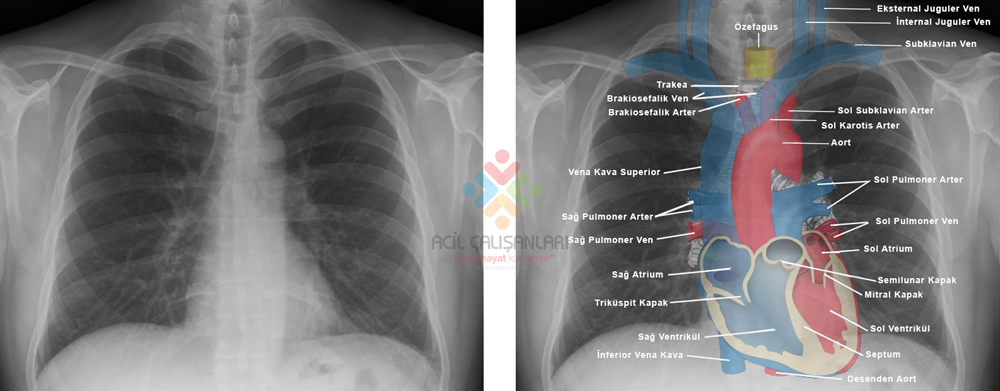

Grafide Anatomik Yapılar ve Çizgiler

Kalp-Mediasten: Kardiotorasik oran değerlendirilmeli ve erişkinler için 1:2 sınırının altında olup olmadığı, kalbin konfigürasyonu ve olası büyüklük farkları değerlendirilmelidir. Kalp kontrol edildikten sonra aorta ve pulmoner arterlerin kalibrasyonları değerlendirilir.

Trakeanın orta hat ile ilişkisi ve çapı değerlendirilmelidir. Yetişkinde yaklaşık 1,8-2,2 cm olarak çap ölçülür. Devamlılığındaki ana bronşların açıklığı ve olası kitleler kontrol edilmelidir.

Hiluslar başlıca pulmoner artreler, kısmen süperiyor pulmoner venlerden kaynaklanır. Her iki hilus genişliği kitle ve lenfadenopati gelişimlerinin değerlendirilmesi için önemlidir. Sol hilus yaklaşık olarak sağ hilustan 25 mm daha yukarda yer alır, eşit seviyede olabilir. Hilusların dansitesi aynı olmalıdır ve dış konturu konkav veya düz olmalıdır. Bu yapılar ile birlikte mediasten konturlarının değerlendirilmesi ile olası kitleye bağlı genişlemeler kontrol edilmiş olur.

Kalbin ağırlığı nedeniyle sol diafragma sağ diafragmaya göre daha 1,5-3 cm aşağıda yer alır. Solda akciğer tabanı ile mide havası arasındakş kalınlık 1 cm den küçüktür. Mide içinde veya splenik fleksurada aşırı miktarda gaz bulunması halinde sol diafragma sağ taraftan daha yukarıda yer alabilir. Her iki diafragma arası yükseklik farkı üç santimetreden daha fazla olmamalıdır.